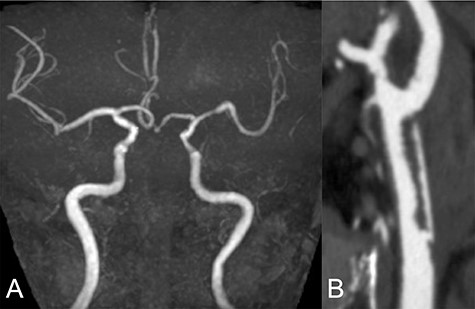

Repeated DWI images showed no significant expansion of the infarction, and complete recanalization of the left CCA was confirmed on MRA 2 weeks after initial onset (Fig. 2A). CTA revealed an irregular arterial wall and pseudo-lumen located in the CCA, extending to the bifurcation, suggesting an isolated left CCA dissection without the dissection extending to the aorta (Fig. 2B).

Two weeks after stroke onset, MRA revealed a complete recanalization of the left CCA (A). CTA also showed an irregular vessel wall and a pseudo-lumen located starting at the left CCA extending to the carotid bifurcation (B).